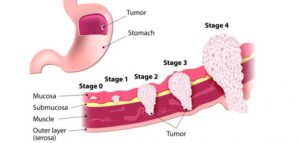

سرطان المعدة الذي يطلق عليها أيضًا السرطان المَعدي هو نمو لخلايا يبدأ داخل المعدة. تقع المعدة في منتصف الجزء العلوي من البطن تحت الضلوع مباشرة.